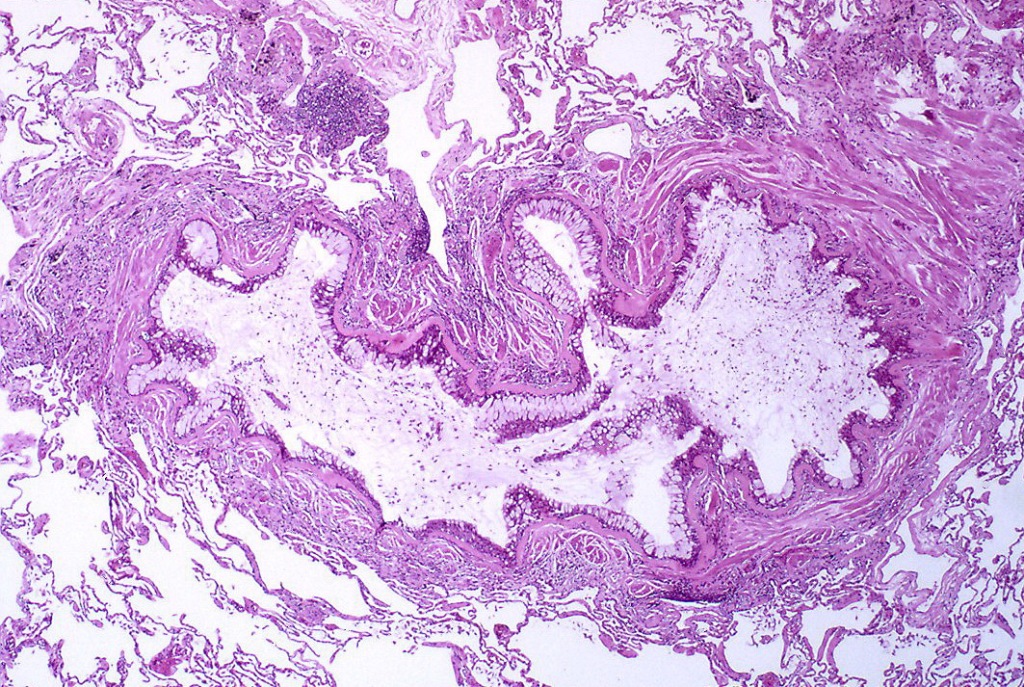

由黏液状的渗出物、杯状细胞化生和上皮基底膜导致的细支气管内腔阻塞在哮喘病人体内增厚。

随着显微镜和新染色技术的逐渐采用,细胞及其成分可以被更清晰地观察。病理学研究发现了一些支持哮喘发作时肺部出现炎症和黏液阻塞的证据。法国著名神经病学家夏科(JeanMartinCharcot)描述了一名患支气管炎的女性痰液中的特殊晶体,德国临床医生莱登(ErnstVictorvonLeyden)进一步阐述了它的来源和性质,认为这些晶体可能是支气管痉挛的原因(这种晶体后来被命名为Charcot-Leyden晶体)。几年后,另一位德国医生柯什曼(HeinrichCurschmann),描述了哮喘患者痰液中的螺旋结构(即Curschmann螺旋体),并表明螺旋和晶体都是在较小气道中形成的黏液栓。随后,在哮喘患者的痰液和血液中鉴定出嗜酸性粒细胞(一种白细胞)。Charcot-Leyden晶体和嗜酸性粒细胞之间存在明显的相关性,证实了炎症渗出物在支气管哮喘中发挥关键作用的推测。医学工作者开始坚信:晶体、螺旋结构形成的黏液栓等炎性渗出物在支气管哮喘中发挥了关键作用。19世纪末,支气管痉挛、黏膜炎症两种哮喘理论的支持者间关系持续紧张,许多专业人士开始有了中间立场,认为痉挛、炎症在哮喘患者身上是并行、共存的过程。